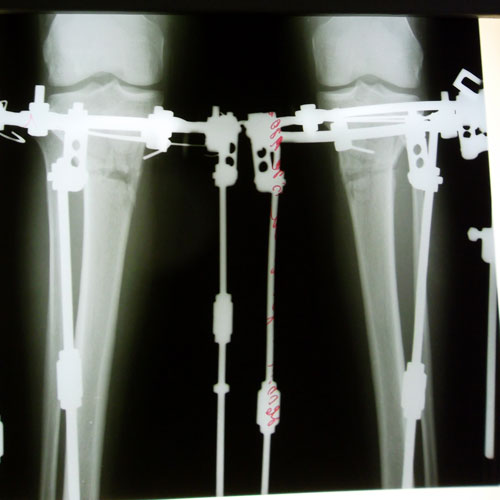

Понедельник , 20-ый день со дня операции. Сегодня мои ножки отдыхают от круток. С утра к нам пришел мастер по маникюру и педикюру ну и мы не задумываясь воспользовались ее услугами! Привели в порядок свои ноготочки , разнообразили наши будние дни и немного подняли себе настроение!

. После обеда я собралась в путь дорогу на первый этаж для снятия рентгена, а для этого мне необходимо преодолеть спуск по лестнице

я даже представить не могла как буду это делать ...но оказывается БОЛЬШЕ БОЯЛАСЬ .. Спуск и подъем по лестнице преодолела спокойно и безболезненно, конечно же не без помощи нашей любимой и отзывчивой Мариши ! Она ни на шаг не отходила от меня и всю дорогу подстраховывала! Гляжу на свои снимки и не могу поверить , что это мои косточки !!! Просто фантастика!

. Посмотрим что завтра скажет Николай Николаевич .....